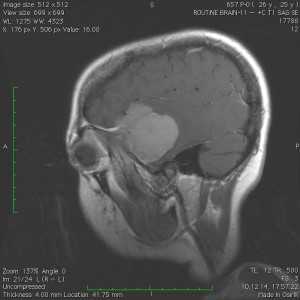

Пациентка В., 25 лет. В возрасте 9 лет перенесла острый лимфобластный лейкоз, по поводу чего проводилась лучевая терапия.

За 2 месяца до поступления в стационар появилась боль в левой височной области, левом глазном яблоке, слезотечение. Консультирована офтальмологом — выявлено высотные левого глазного яблока на 6 мм, по сравнению с правом глазным яблоком, а также признаки внутричерепной гипертензии в виде застойных дисков зрительных нервов. При МРТ выявлена больших размером внемозговая опухоль средней черепной ямки с гиперостозом и распространением в глазницу слева.

Выполнена операция — удаление менингиомы крыльев клиновидной кости с резекцией гиперостоза и использоваием интраоперационной метаболической навигации (ультрафиолетовая флюоресцентная микроскопия)